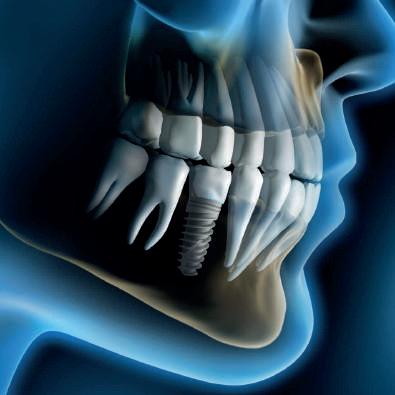

La perdita dei denti è un problema che affligge milioni di persone in tutto il mondo. Carie, traumi, malattie gengivali e altre condizioni patologiche possono portare alla necessità di estrazioni dentarie, causando disagi significativi sia dal punto di vista estetico che funzionale.

Tuttavia, una svolta rivoluzionaria nella medicina dentale potrebbe essere all’orizzonte: un nuovo farmaco per la ricrescita dei denti è previsto per il 2030 e i test sull’uomo inizieranno a settembre. Una scoperta rivoluzionaria

La possibilità di far ricrescere i denti persi è stata a lungo considerata fantascienza, ma recenti progressi nella biotecnologia stanno trasformando questa visione in realtà. Il farmaco, sviluppato da un team di ricercatori giapponesi, mira a stimolare le cellule staminali dentali, promuovendo la rigenerazione dei tessuti dentali persi. La chiave di questa innovazione risiede nella comprensione approfondita dei meccanismi genetici e molecolari che regolano la crescita dei denti.

Una start-up dell'università di Kyoto, nata 4 anni fa, sta sviluppando un farmaco anticorpale descritto come "il primo al mondo per la ricrescita dei denti" e da settembre comincerà a testarlo sull'uomo, dopo i risultati positivi ottenuti sugli animali senza effetti collaterali di rilievo. L'obiettivo dei ricercatori è arrivare sul mercato nel 2030, riporta la testata nipponica 'The Mainichi'.

I topi trattati con il farmaco hanno mostrato una ricrescita significativa dei denti, suggerendo che una simile risposta potrebbe essere ottenuta anche negli esseri umani. La transizione ai test sull’uomo rappresenta un passo cruciale verso l’applicazione clinica di questa tecnologia rivoluzionaria.

Il processo di sperimentazione clinica I test sull’uomo, che inizieranno a settembre, seguiranno un rigoroso protocollo di sperimentazione clinica, suddiviso in diverse fasi. La fase 1 coinvolgerà un piccolo gruppo di volontari sani per valutare la sicurezza del farmaco e determinare

il dosaggio ottimale. Se questa fase avrà successo, si passerà alla fase 2, dove un numero maggiore di partecipanti, inclusi individui con problemi dentali specifici, sarà coinvolto per valutare l'efficacia e monitorare eventuali effetti collaterali. La fase 3, infine, includerà un ampio gruppo di pazienti e avrà lo scopo di confermare i risultati precedenti, confrontando l'efficacia del farmaco con i trattamenti esistenti. Se tutte le fasi di sperimentazione avranno esito positivo, il farmaco potrebbe essere approvato dalle autorità regolatorie e disponibile per l’uso clinico entro il 2030.

Implicazioni per la medicina dentale

L’introduzione di un farmaco capace di stimolare la ricrescita dei denti avrebbe implicazioni enormi per la medicina dentale. Attualmente, la perdita dei denti viene trattata principalmente con protesi dentarie, impianti e ponti. Sebbene efficaci, questi trattamenti non sono esenti da complicazioni e richiedono manutenzione a lungo termine. Un farmaco rigenerativo offrirebbe una soluzione naturale e permanente, riducendo la necessità di interventi chirurgici e migliorando significativamente la qualità della vita dei pazienti.

Inoltre, la capacità di rigenerare i denti avrebbe anche un impatto economico significativo. Il costo dei trattamenti dentali può essere proibitivo per molte persone, e una terapia rigenerativa potrebbe ridurre i costi a lungo termine associati alla manutenzione e sostituzione delle protesi dentarie. Questo potrebbe rendere le cure dentali più accessibili a un numero maggiore di individui.